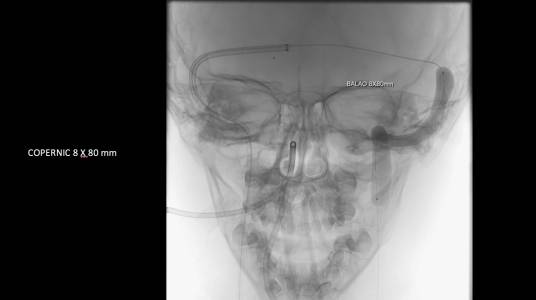

O caso clínico apresenta a utilização de materiais com finalidades primárias para trombectomia mecânica no contexto de acidente vascular cerebral (Rebar 27 + Solitaire) e o balão Copernic RC (Balt) comumente utilizado auxiliando na embolização de fístulas durais para os seios, auxiliando no processo de trombectomia mecânica no contexto de extensa trombose venosa cerebral.